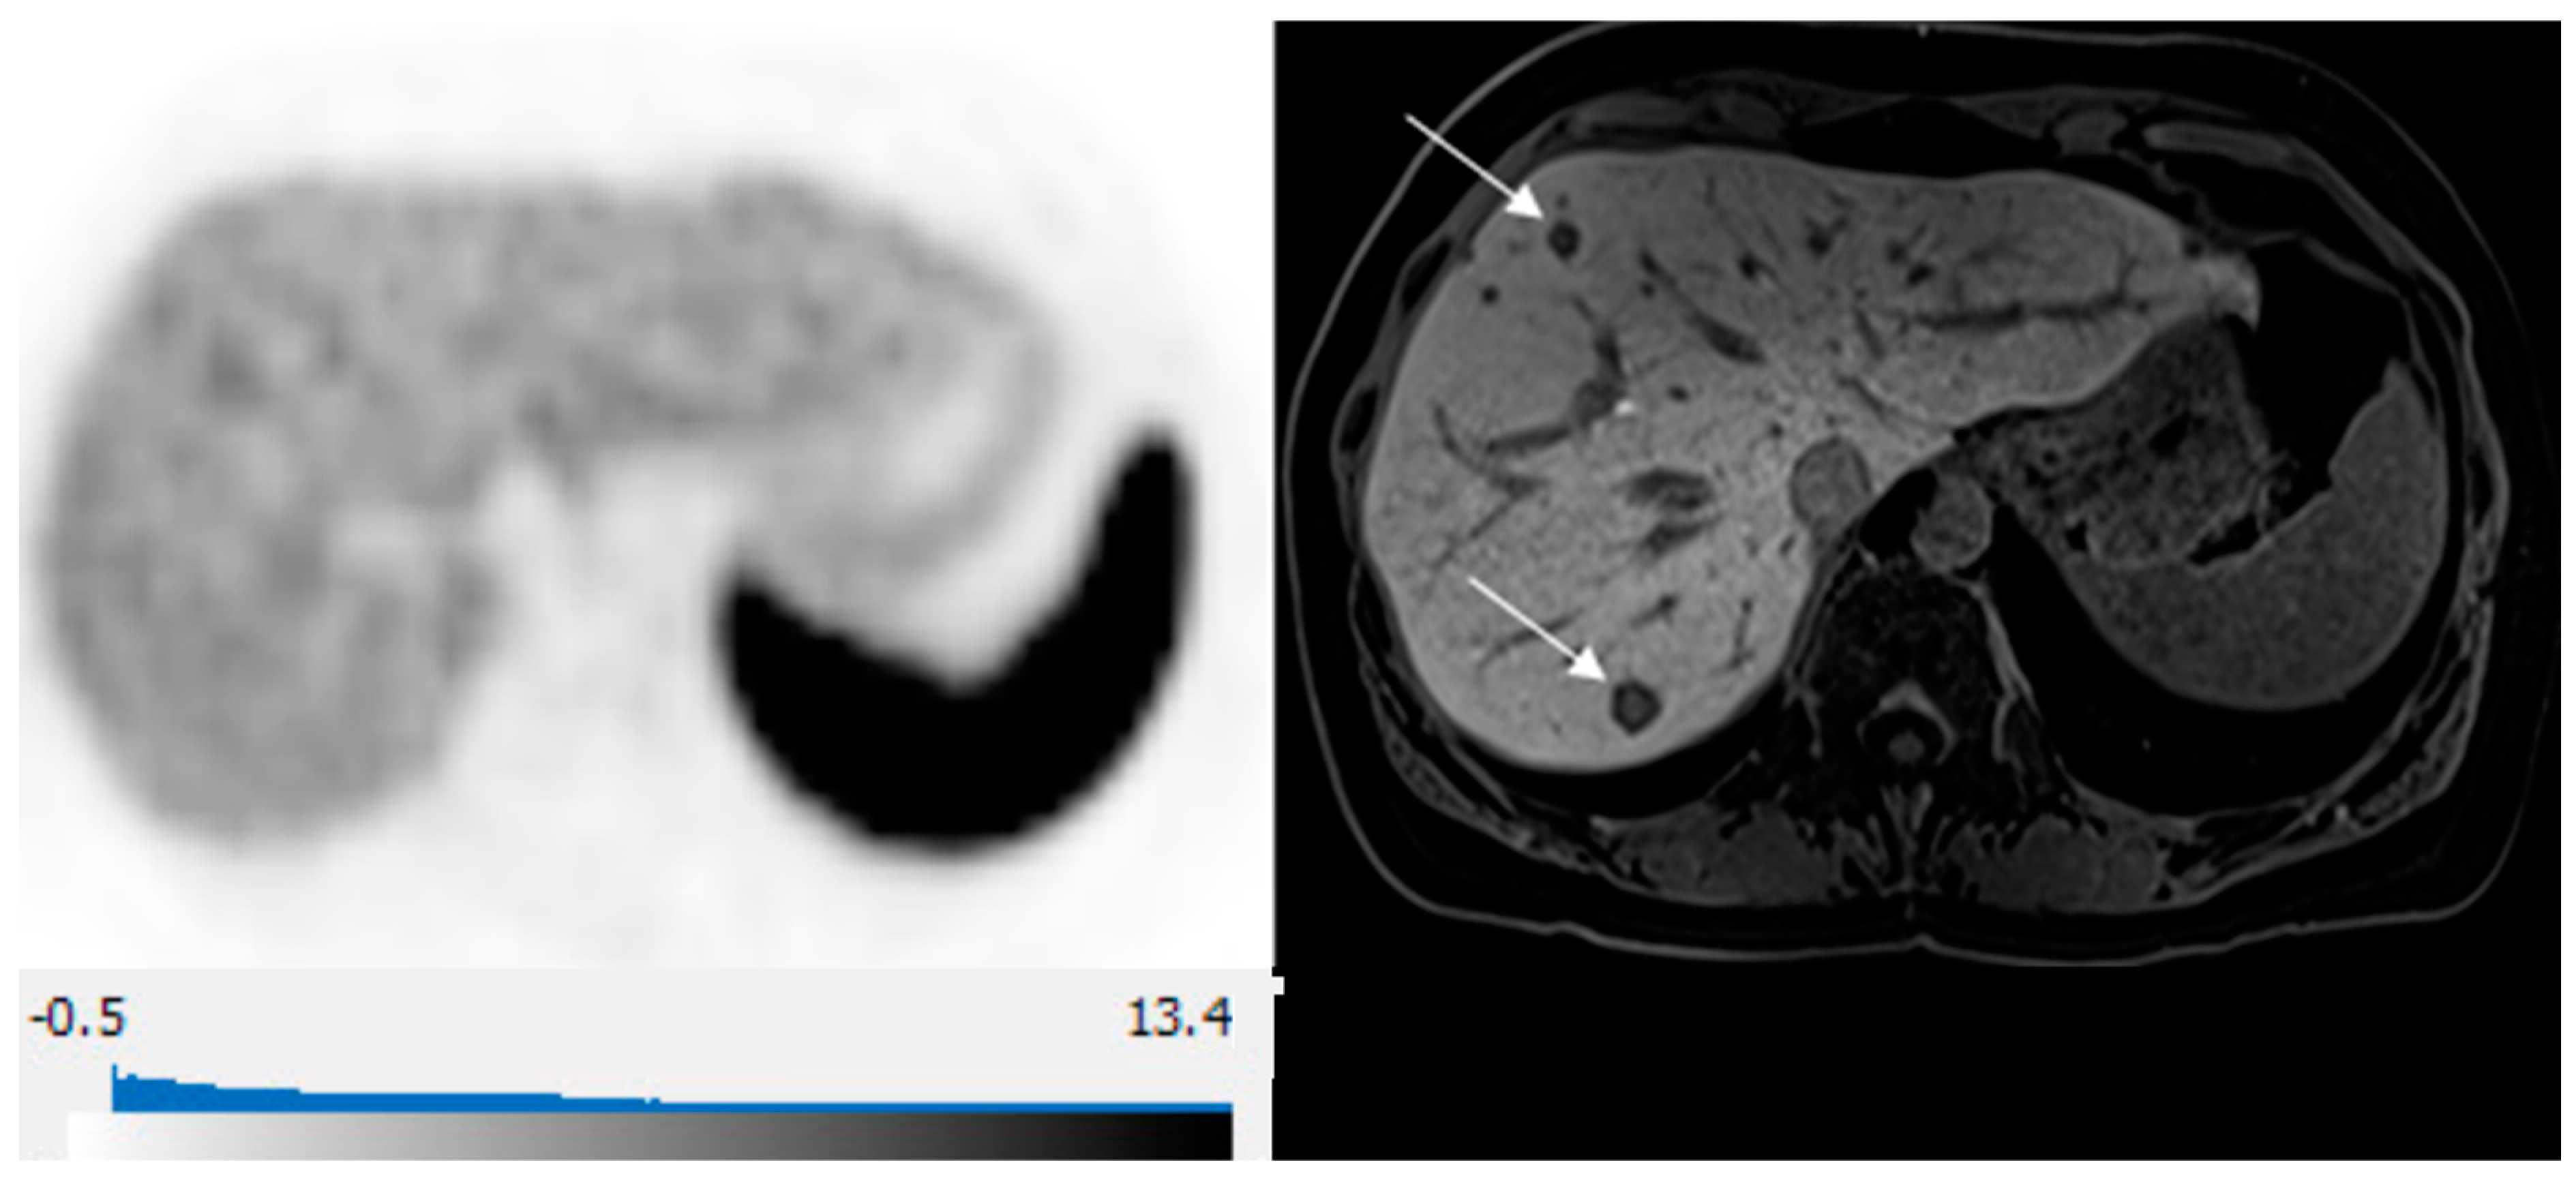

3. Results